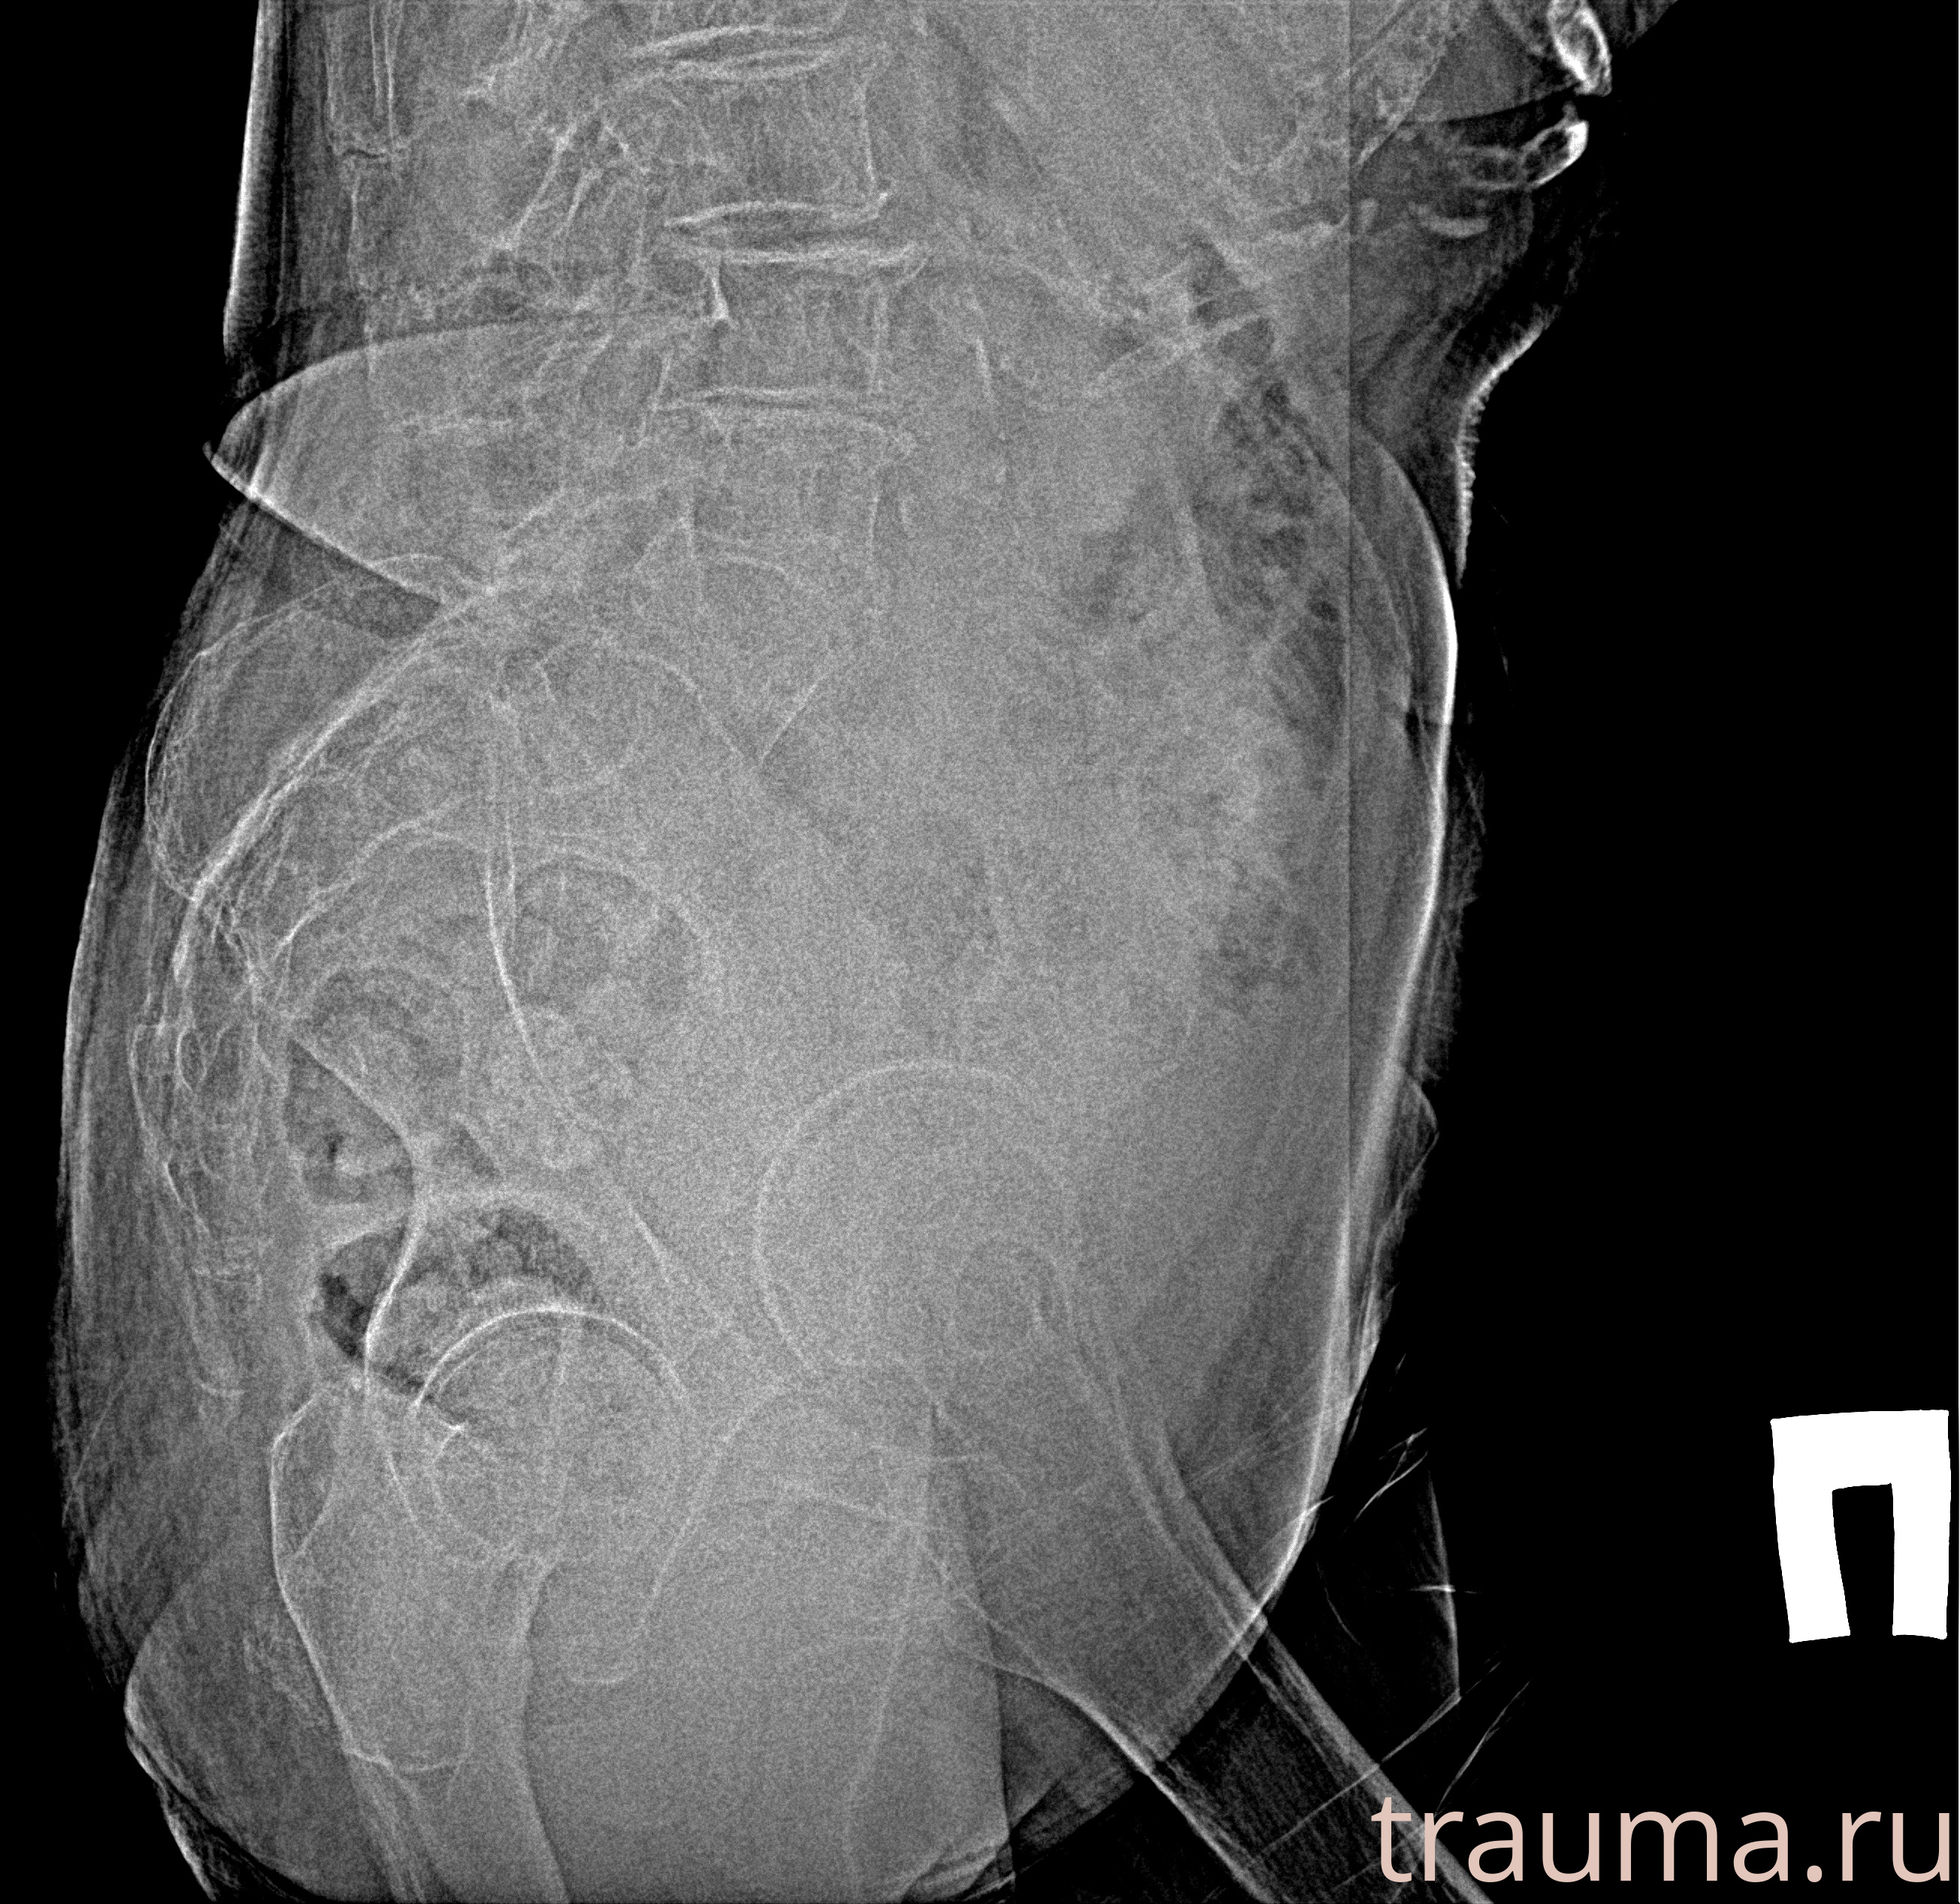

Рентген на дому: по вашему адресу приезжает врач-рентгенолог, травматолог-ортопед с мобильным рентгеновским аппаратом, проводит диагностику травмы или заболевания, делает необходимые рентгенограммы, дает рекомендации по дальнейшему лечению. Получить качественные снимки в домашних условиях возможно благодаря уникальной методике, разработанной МосРентген Центром для института  Склифосовского